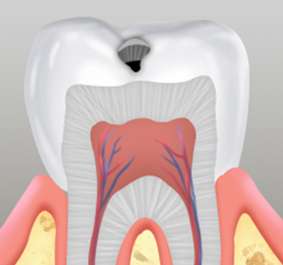

대개 잘 보이지 않는

한두개의 점 모양

급격한 온도차에

의한 통증 발생

충치부위를 제거한 후 치과용 충전재료를 충전하는 방식이며 치아 손상이 경미한 경우에 진행합니다.